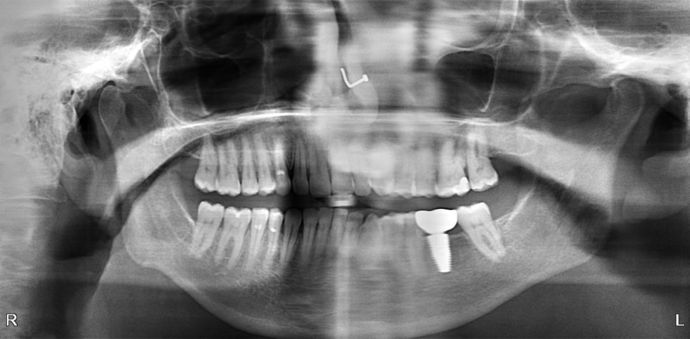

Fracture of a root canal tooth required an extraction followed by an implant and implant crown